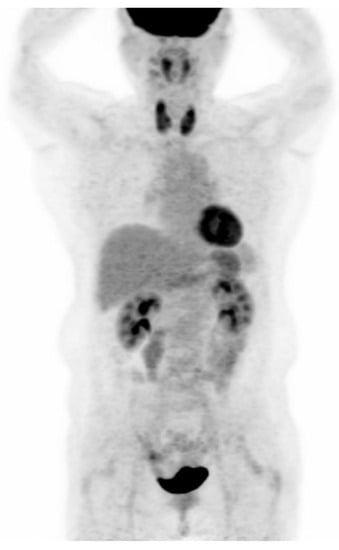

2.4. 18F-FDG PET/CT